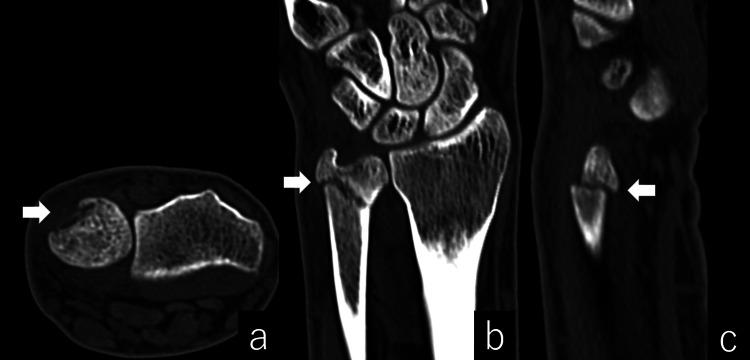

尺骨远端干骺端骨折通常采用保守治疗,临床效果良好。保守治疗尺骨远端干骺端骨折后发生尺侧腕伸肌(ECU)肌腱病的情况尚未见报道。我们报告一例20岁的大学棒球运动员,在保守治疗尺骨远端干骺端骨折后发生了ECU肌腱病。骨折部位的轻微台阶样畸形以及作为接球手的反复运动被认为是导致ECU肌腱病的原因。临床医生应注意在运动或职业中反复加载ECU的尺骨远端干骺端骨折后发生的ECU肌腱病。